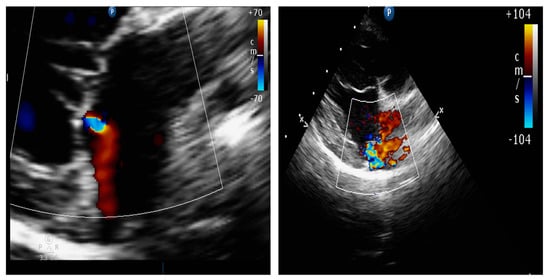

4.8.2. Presence of Vena Contracta

| Quantitative assessment of mitral regurgitation | Commonly used in human patients, but seldom utilized in canine patients and practical application is limited (defining EROA and flow convergence shape can be challenging) [60]. |

| Flow convergence area measurement by PISA | A standard gold method in humans, not routinely performed in cardiologic evaluation in dogs (PISA quantification showed a wide range of RF in a clinical study) [61,62]. |